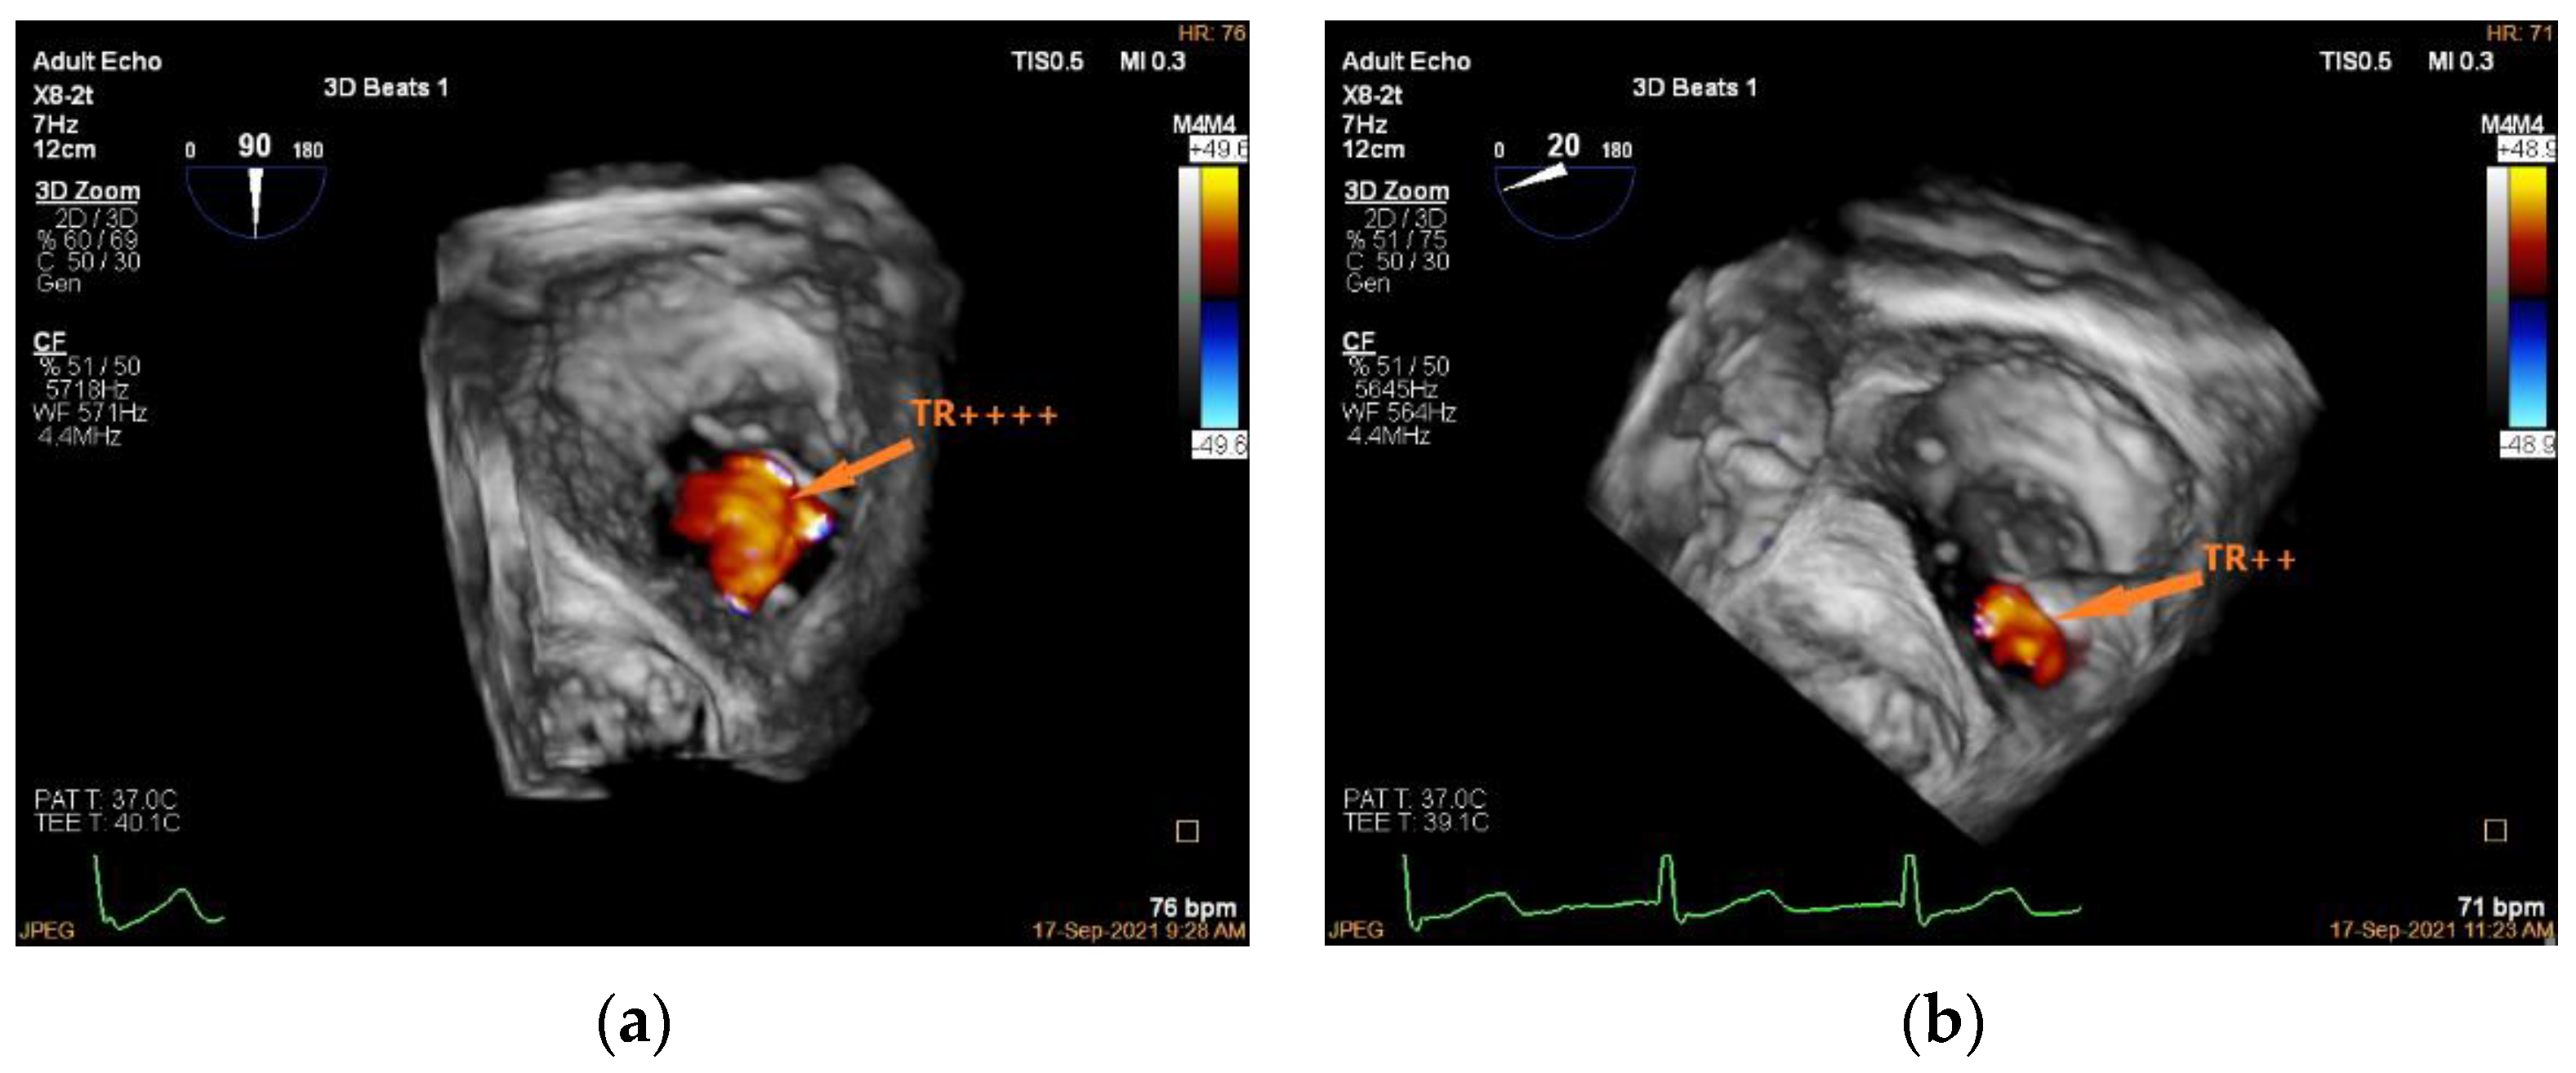

3.5. Valve Function Assessment

| Step 4. Valve function assessment | 2D and 3D (preferable) color Doppler imaging | Multiple views required | 3D color Doppler imaging is preferred as tricuspid intervention results in highly complex valve geometry |